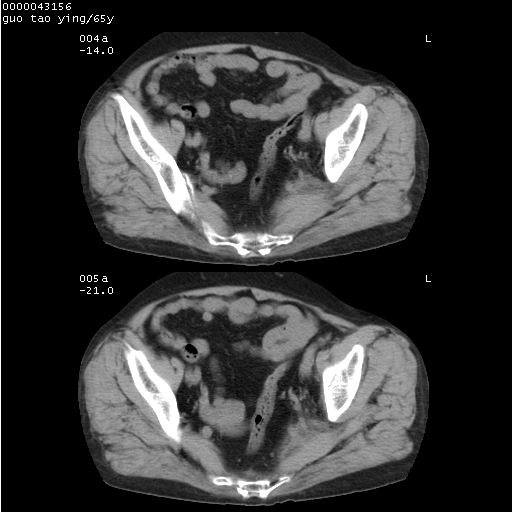

以下是引用黑白光影在2008-1-30 13:22:00的发言:[br]支持左耻骨骨折。[br]未见骶骨骨质明确破坏改变。[br]经楼主提示(勿局限于外伤)。考虑为右侧腹股沟直疝。[br][br][br][br]